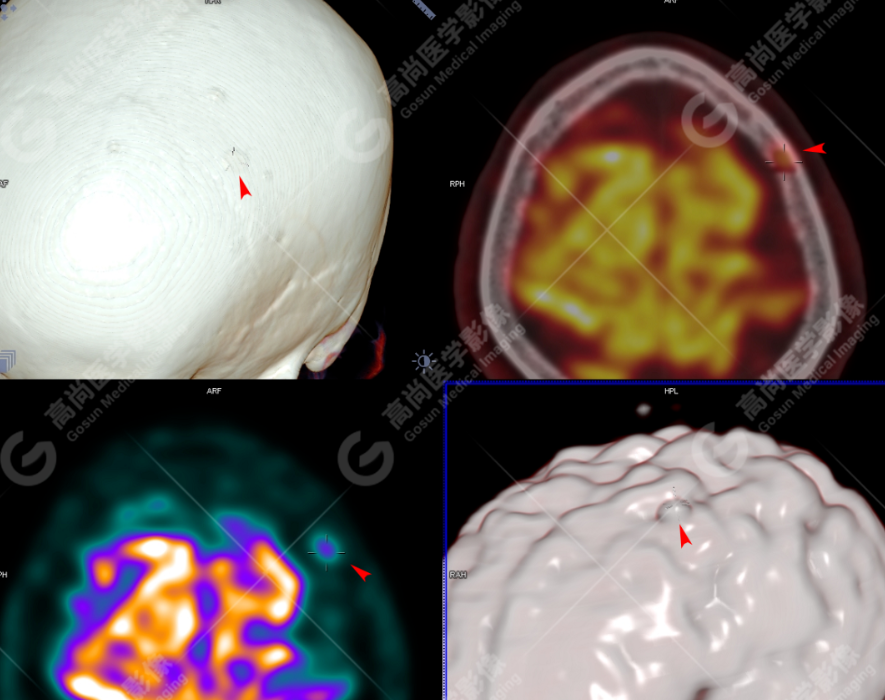

颅骨、寰椎前弓左侧份、第 6 颈椎、双侧肩胛骨(右侧为著)、左侧第 4 肋骨、第 1 胸椎、第 4 胸椎、第 2 腰椎及附件、第 4 腰椎及附件、骶骨、右侧髂骨、左侧坐骨结节、左侧股骨颈、双侧股骨小转子等均不同程度骨质吸收、破坏,其中右侧肩胛骨、左侧第 4 肋骨及骶骨右侧份软组织肿块影形成,上述病变均考虑恶性肿瘤(血液系统来源,多发骨髓瘤可能性大),建议右侧髂骨翼穿刺活检明确。

(4)PET-CT 影像表现:在溶骨性破坏区出现相重叠的 18F- FDG 高代谢区;通常呈弥漫性高代谢区。